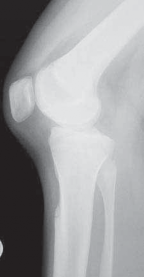

41. The reduction is confirmed with fluoroscopy or a radiograph (

TECH FIG 10

).

A B C

TECH FIG 10 • A. PCL tibial avulsion in a patient with a previous ACL reconstruction. B,C. Lateral and PA radiographs after fixation of the tibial avulsion.